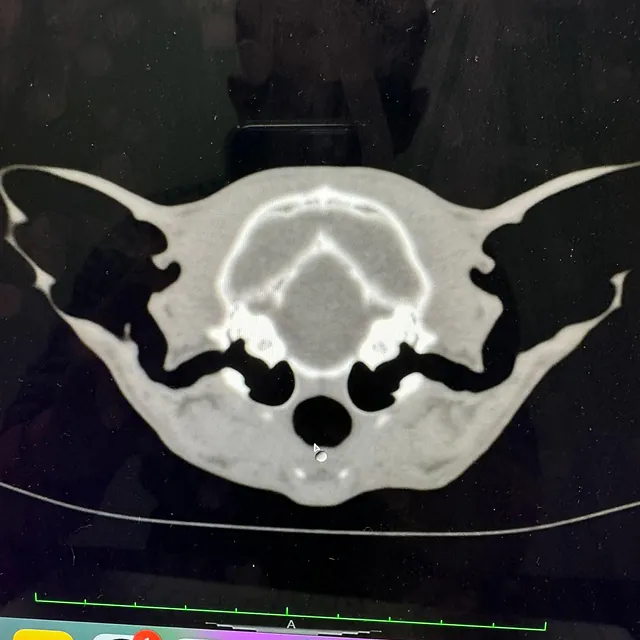

CT Scanner

Our CT scanner was installed at our Tunstall practice in 2017 and was the first permanent veterinary CT scanner in our area. It is available 24 hours a day to both our own patients and as a referral service to surrounding practices.

Computed Tomography (CT) involves the use of x-rays to take thousands of pictures of cross-sections of the body. These can then be built up into a 3D image and used to create a detailed reconstruction of the patient. This is a thorough and prompt way to reach a diagnosis and enable quicker treatment. The CT scanner is particularly useful for the diagnosis and planning of complex surgical procedures and medical conditions.

We are able to obtain full results from external specialists and also, we are lucky that one of our own vets - Charlie Green - is an Advanced Practitioner is Diagnostic Imaging and a General Practitioner in CT; meaning she can read our CT scans on site and enhance surgical planning and treatments.

Brian’s CT Scan

The first CT scan we carried out was done on Clive's dog, Brian's, nose. We found a sarcoma in his upper jaw, and successfully removed it. A CT was needed to ensure the surrounding area was in good health.